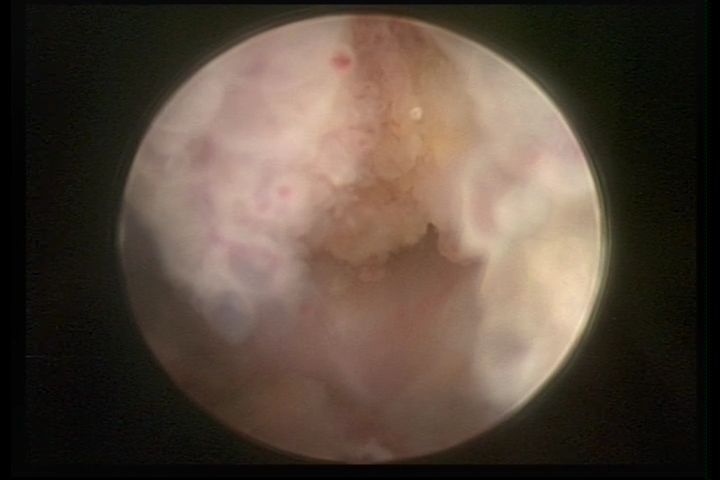

Este pode apresentar uma gama variável de aspectos macroscópicos, com aspecto pseudopolipoide; lembrando tecido cerebroide ou com reação deciduoide; a vascularização superficial é mais evidente e com vasos em formatos de saca-rolha ou espirais visualizando também a vascularização com atipias, com aumento do calibre dos vasos superficiais, pode ser encontrado também tecido em necrose, poderá haver pequenos dendritos (papilomatoso).